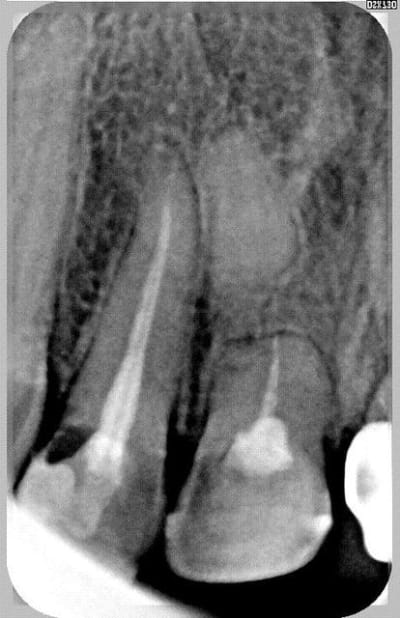

bilan 2 incisives centrales cassées net 1,5 mm sous le rebord alvéolaire

cassé trop bas pour tracter...

11 21 réduit 01 wfhbkx - Eugenol

Rx 11 21 02 reduit kwsfll - Eugenol

Rx 11 21 reduit uoydvy - Eugenol

ce n'est peut être pas très visible sur la radio, mais c'est précisément ce qui a été fait:

je n'ai obturé que le 1/4 apical (je ne voulais pas que le ciment fuse dans la fracture lors de la condensation : donc j'ai ajusté la hauteur de cône necessaire que j'ai ensuite condensé à chaud avec des pluggers rouges et jaunes,

j'ai ensuite placé une tenon en fibre de verre (les seuls tenons suffisamment long pour assurer un brochage efficace:

j'ai procédé à la séquence de collage habituelle :

etching / optibond + activateur / compodual pour le scellement du tenon.

j'ai hésité à sceller le tenon au verre ionomère (moins sensible à l'humidité :

rétrospectivement au regard des arguments de ploc cela aurait peut être suffit.